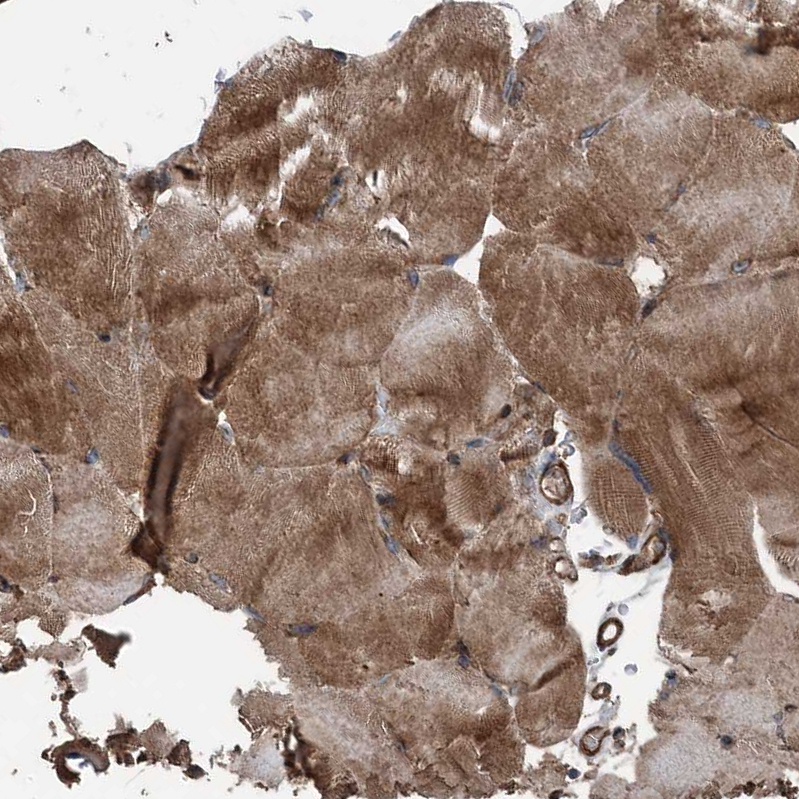

Immunohistochemical staining of human pancreas shows strong cytoplasmic-membranous positivity in exocrine glandular cells.